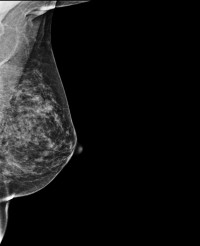

DBT, sometimes called 3D mammography, emerged in the last decade as a powerful tool for breast cancer screening.

The procedure uses an X-ray tube that moves in an arc and takes low radiation-dose projections of the breast from different angles.

Varying the angle allows for multiple data points that can be reconstructed in different ways.

"As a radiologist, tomosynthesis allows viewing of the breast in multiple layers or slices," said study lead author Emily F. Conant, M.D., professor and chief of breast imaging in the Department of Radiology, Perelman School of Medicine at the University of Pennsylvania in Philadelphia. "This ability to scroll through slices of otherwise overlapping breast tissue helps us not only detect more cancers but also better characterise benign or normal areas of the breast."